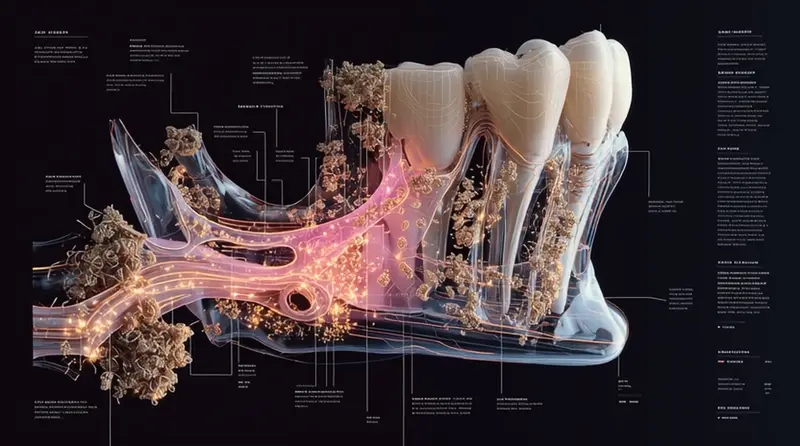

The Silent Destroyer in Your Mouth

Here’s what most people don’t realize: gum disease is like a slow-motion disaster happening right under your nose. It starts quietly – so quietly that 90% of people don’t even know they have it until significant damage has already occurred.

Think of it like termites in your house. You might not see them, but they’re steadily eating away at the foundation. Except in this case, the “foundation” is the bone and tissue that hold your teeth in place.

When you ignore early warning signs, here’s the progression that typically unfolds:

Stage 1: The “It’s Probably Nothing“ Phase Your gums bleed occasionally when you brush. Maybe they’re a little puffy. You think, “I probably just brushed too hard.” This is gingivitis – and it’s completely reversible at this stage. But most people shrug it off.

Stage 2: The “Getting Worse“ Phase Now your gums are pulling away from your teeth. You notice your teeth looking longer. Bad breath becomes a constant companion. You’re entering periodontitis territory, where permanent damage begins.

Stage 3: The “Oh No” Phase Teeth start feeling loose. Chewing becomes uncomfortable. You might even notice pus around your gum line. At this point, you’re looking at potential tooth loss.